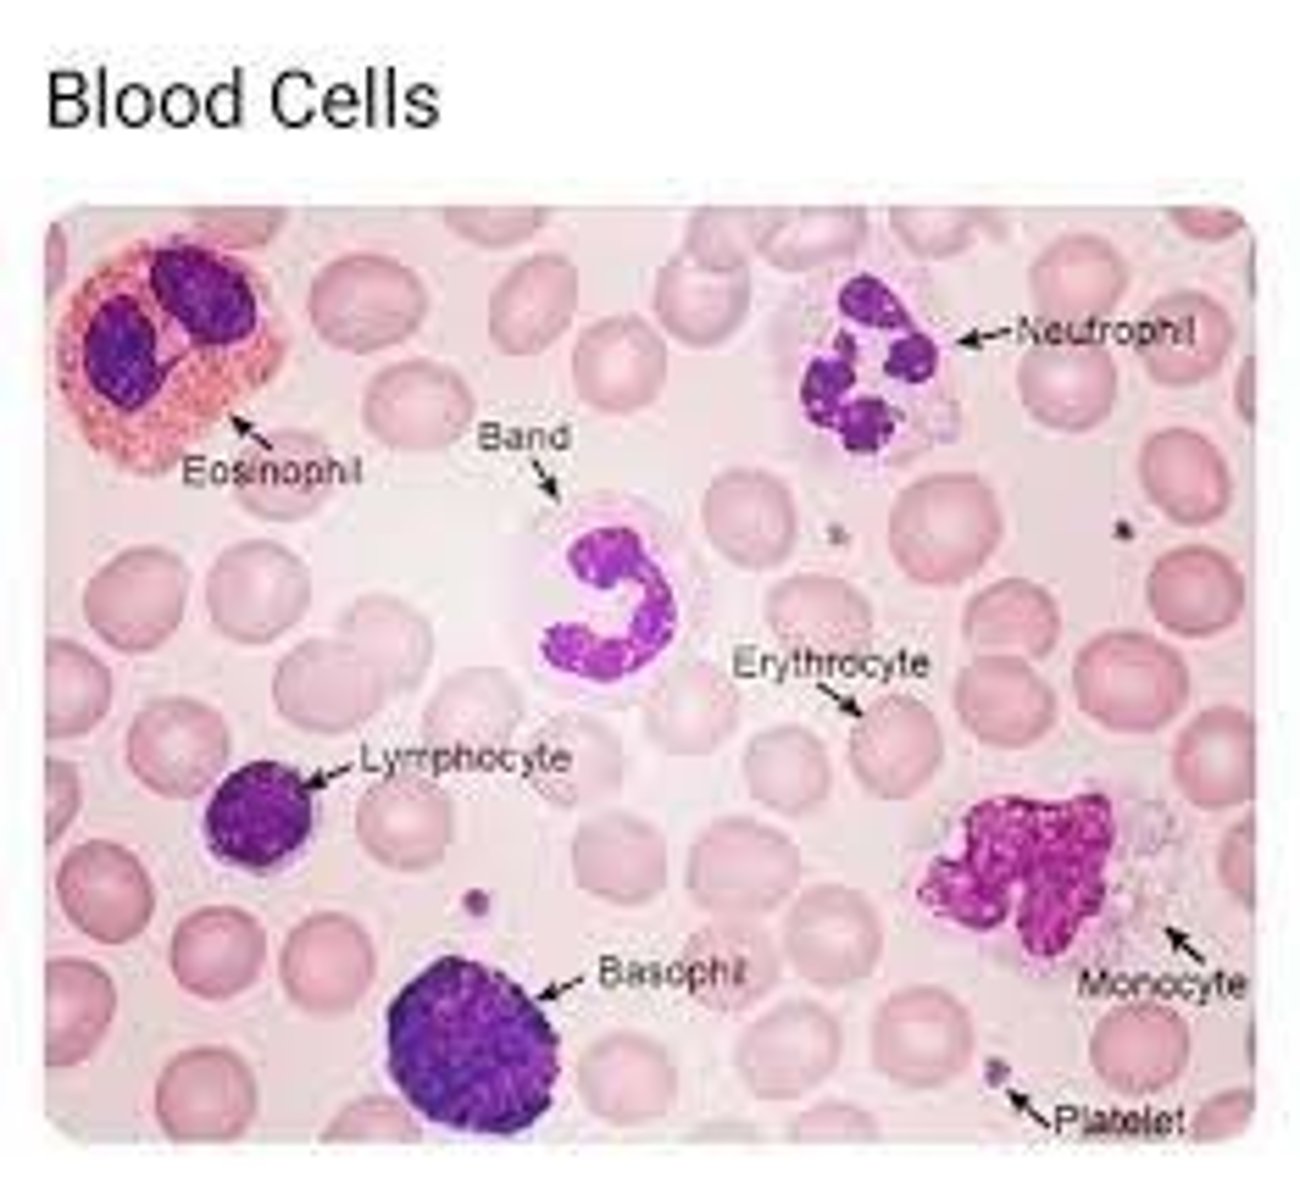

name A - E

A - erythrocyte

B - platelet

C - neutrophil (lobed nucleus)

D - lymphocyte (large nucleus, takes up most of cell)

E - protist

how do you distinguish between a monocyte and lymphocyte under a microscope?

monocyte has a kidney bean nucleus, lymphocyte have a large nucleus that takes up most the cell